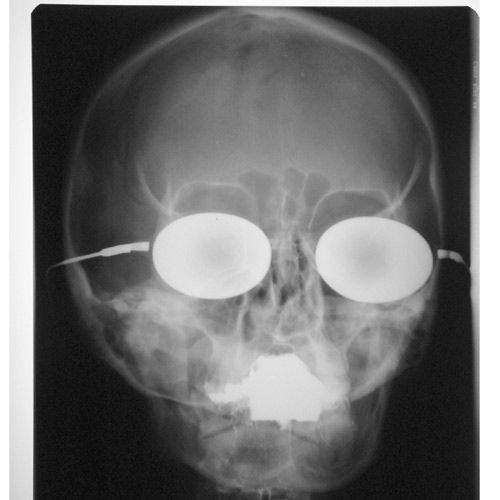

Под рентгеном